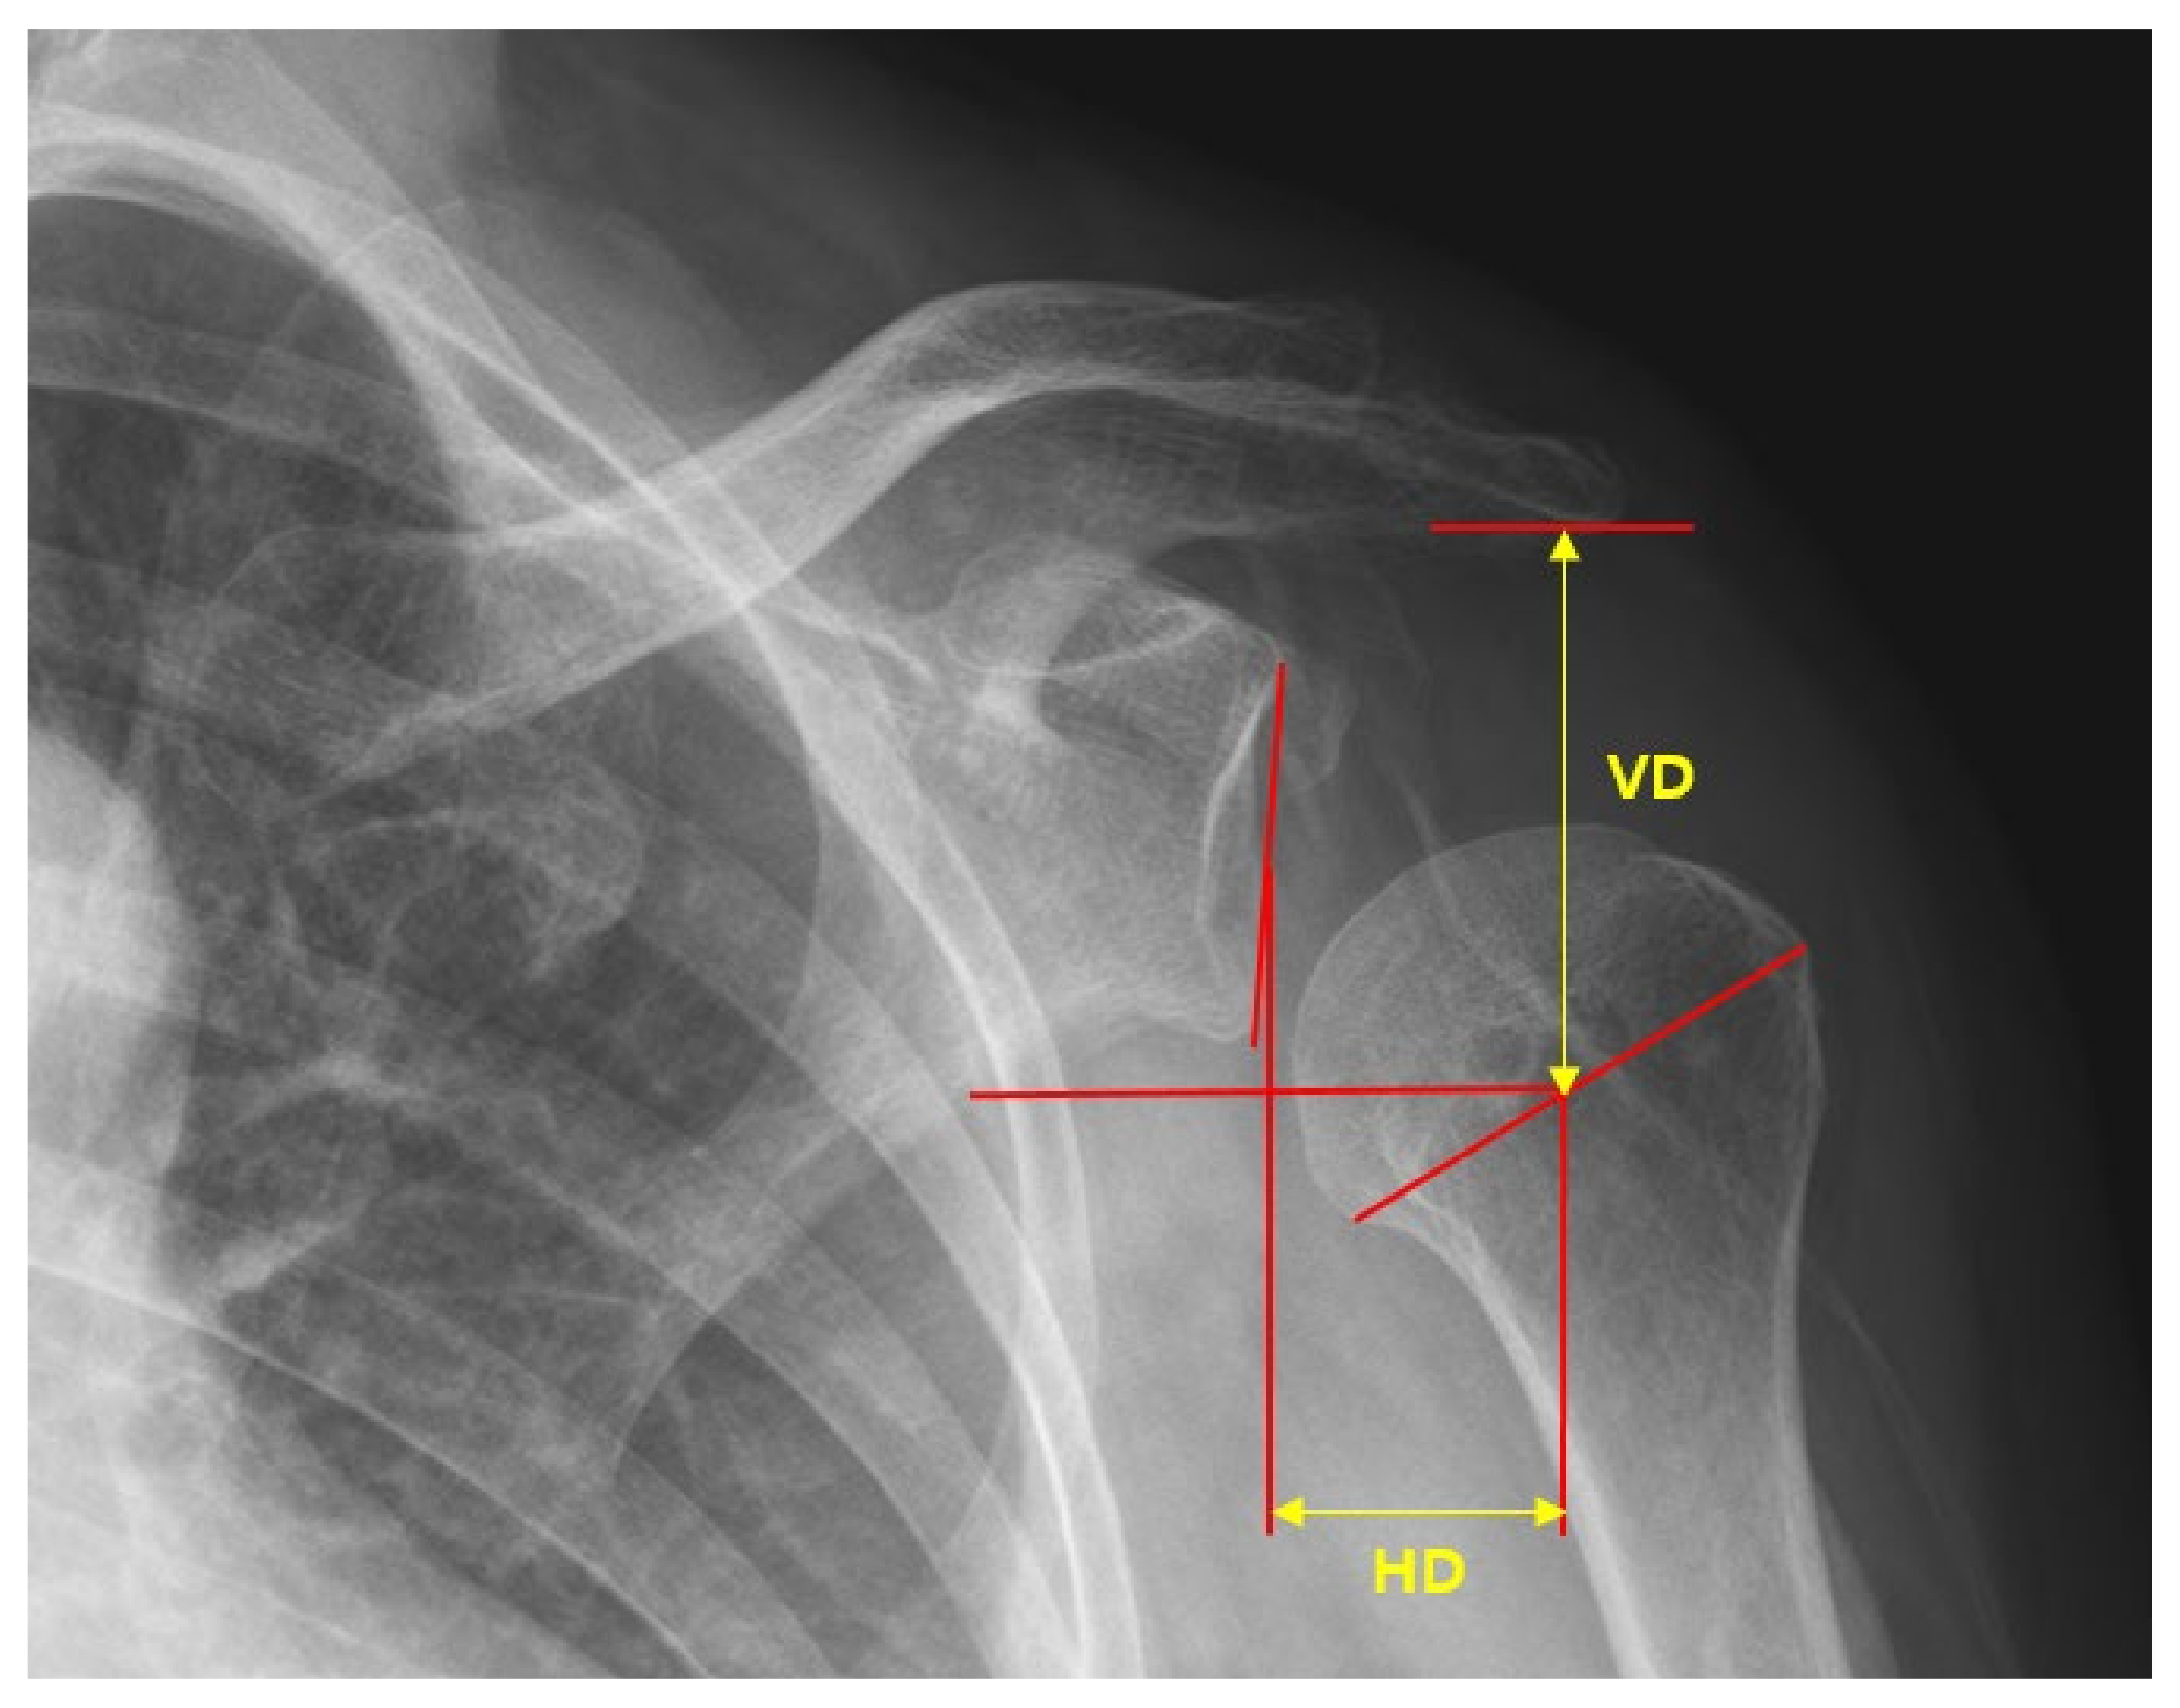

Three analysts measured and analyzed the radiographs in a random order to reduce measurement bias. Distance measurements of shoulder subluxation from a single radiograph were used, as described by Brooke et al. [22]. The central point of the glenoid fossa of the scapula was determined by marking the most distant vertical and horizontal edges. Height and width measurements were then bisected to determine the location of the central point of the glenoid fossa. The central point of the humeral head was determined by measuring the greatest distance that could be horizontally obtained across the head. This line was bisected to provide the central point of the humeral head. The inferior acromial point was determined by identifying the most inferior point on the acromial and lateral surfaces of the acromioclavicular joint. The vertical distance (VD) was measured from the acromial point to the central point of the humeral head. The horizontal distance (HD) was measured from the central points of the humeral head and the glenoid fossa (Figure 4).

Figure 4.

Measurement of horizontal distances (HD) and vertical distances (VD) in a true anteroposterior radiograph.

There were no significant differences in the vertical distance between the elastic dynamic sling and Bobath sling groups. Horizontal distance was significantly reduced in the elastic dynamic sling group compared to that in the Bobath sling group at eight weeks after sling usage (p = 0.006). As shown in Table 4, the horizontal distance of the affected shoulder gradually increased in the Bobath sling group.

Radiological evidence indicated that the Bobath sling caused significant distraction of the humerus in the horizontal plane. Other studies on the Bobath shoulder sling also identified, through the use of radiographs, that the Bobath sling produced a significant lateral displacement of the head of the humerus [27,28]. This study showed similar results as those of a previous study, which showed that horizontal distance gradually increased over time (Table 4).